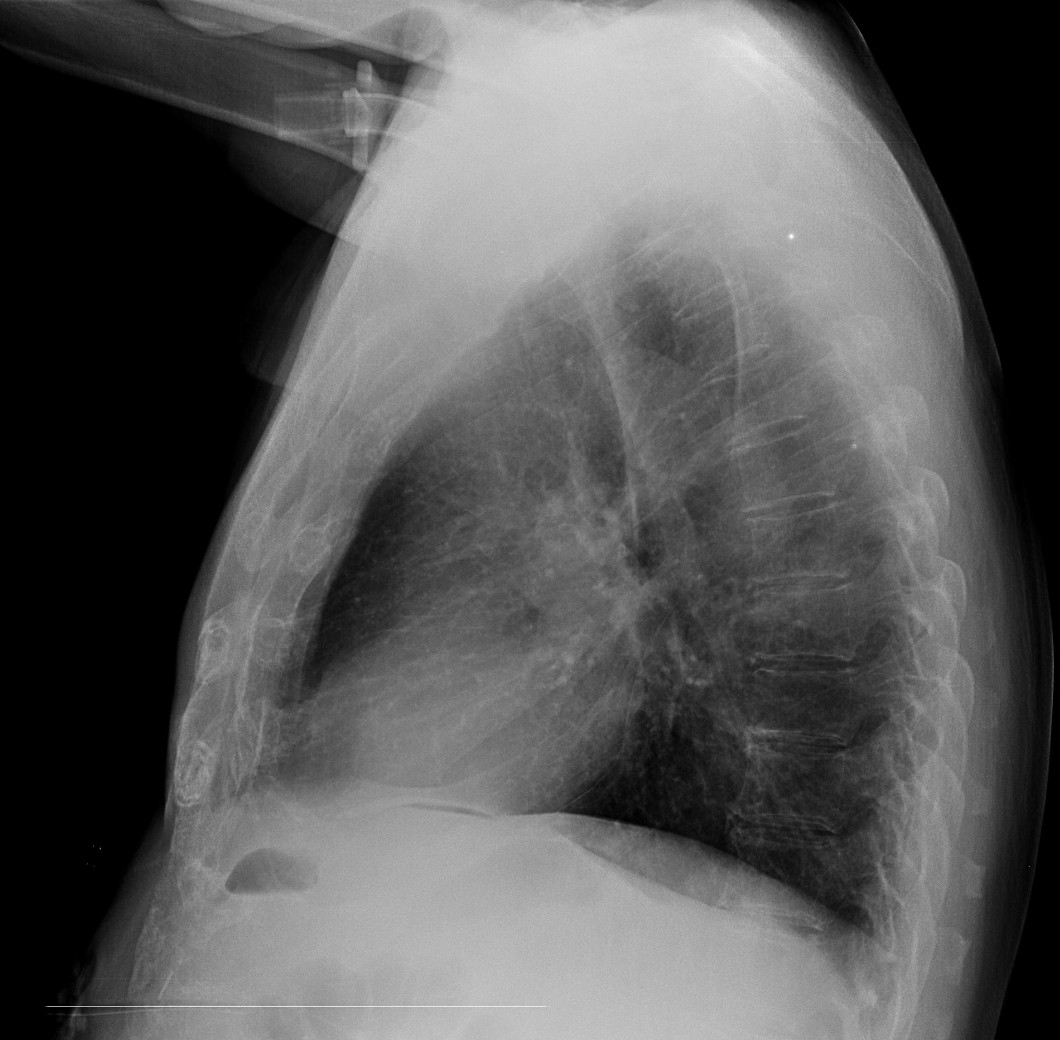

CASO: cáncer de mama. Control anual.

Hallazgos:

- Se observa un aumento de densidad con agrupación broncovascular que produce un borramiento del borde cardicaco derecho; hallazogos compatibles con atelectasia en el lóbulo medio. Véase el TC a continuación: